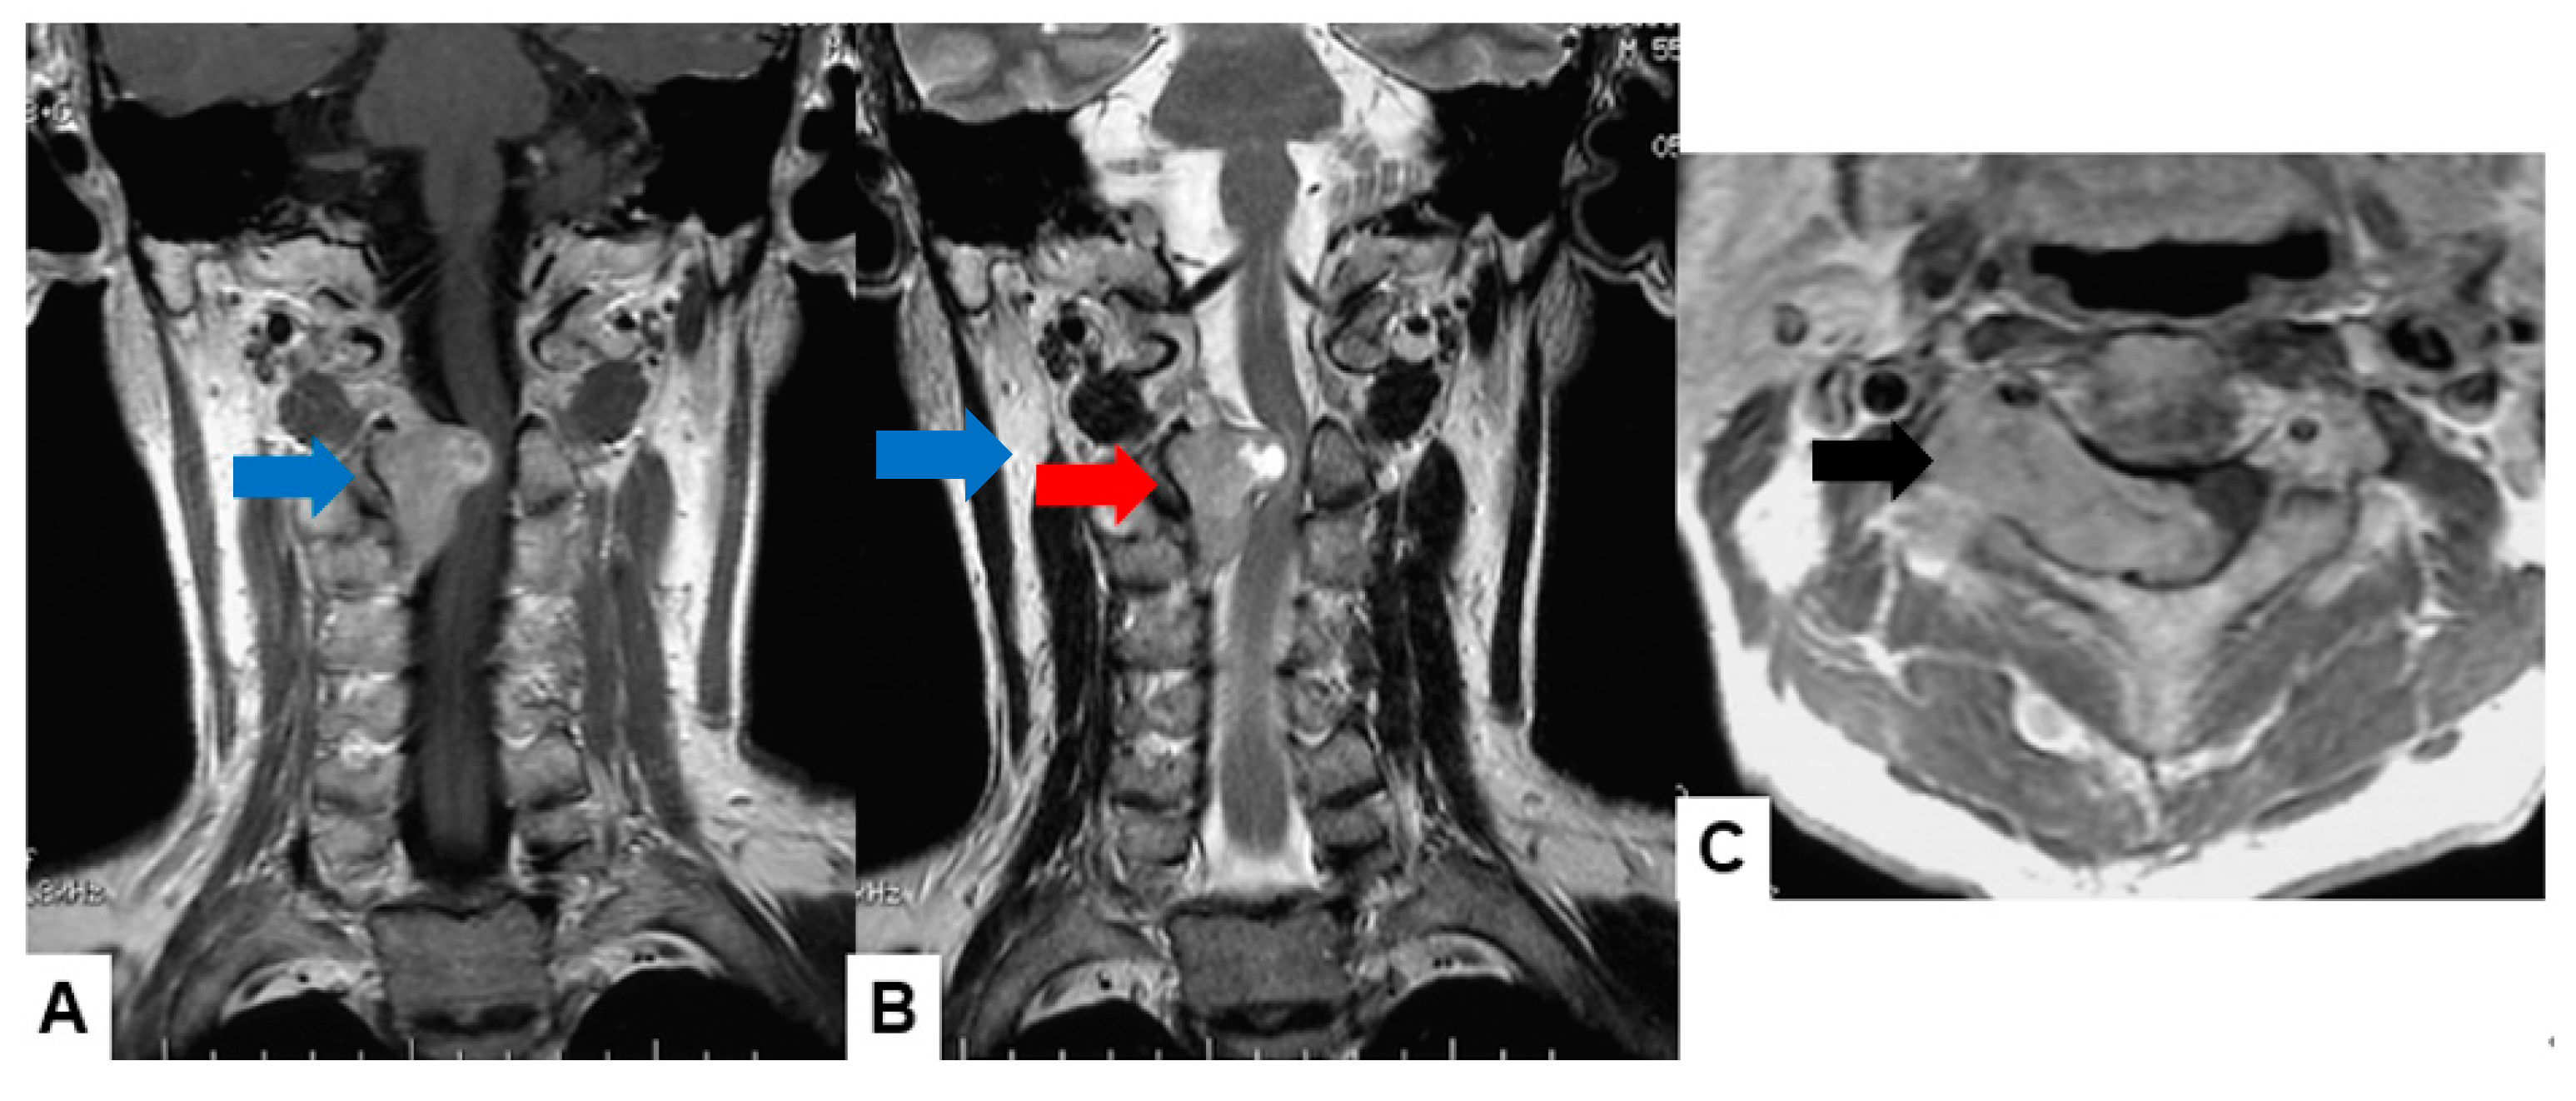

2.1. MRI and CT